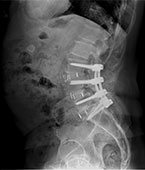

• Patient Cases Before picBefore

• Patient Reviews before image case 1Before Surgery